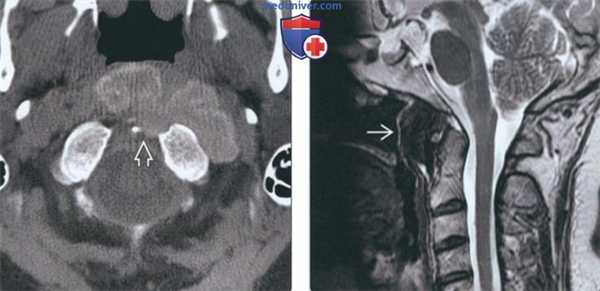

(Слева) На КТ в передних отделах определяется объемное образование с бугристыми краями, имеющее слегка повышенную плотность, напоминающее кальциевое «молочко». Отсутствуют признаки деструкции костной ткани и остеонеогенеза.

(Справа) На MPT(Т2 ВИ) спереди от срединного атланто-аксиального сустава определяется объемное образование с сигналом низкой интенсивности и четкими краями. Сигнал в костном мозге С1, С2 и ската не изменен.